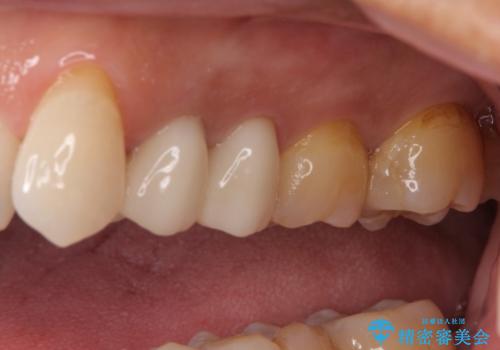

左上で効果を実感して頂き、その後右上もご希望されました。合計3本の歯を治療しました。

腫れもなくなり、見た目もきれいになったため、右上もご希望されて計3本の歯を治療しました。患者様には大変満足して頂きました。